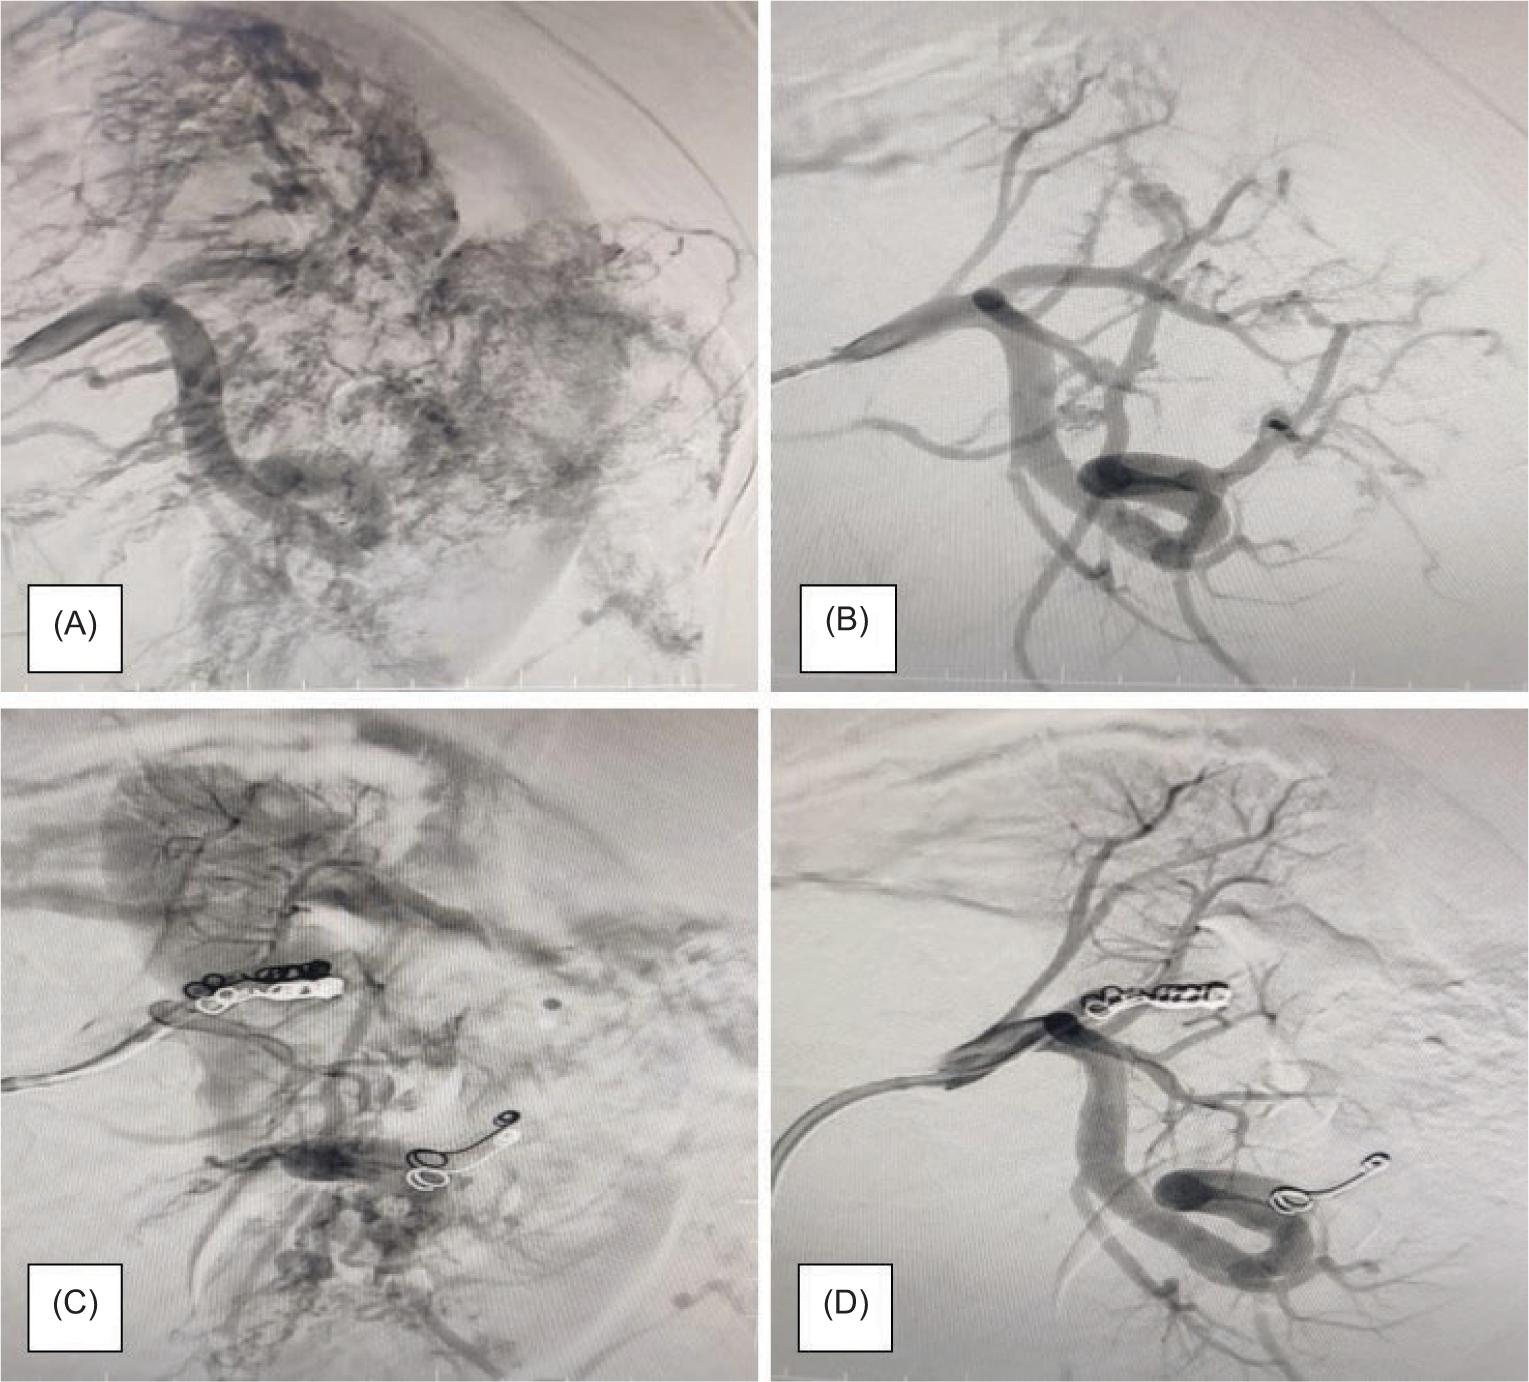

All patients underwent intervention after initial stabilization according to the standard ICU protocol. Three patients underwent emergency angioembolization, and three coils were applied in each case (Figure 2). Two of them developed post-embolization syndrome with post-procedure fever and nausea managed conservatively. One of them continued to have flank pain with a serial drop in hemoglobin level even after embolization that led to an open partial nephrectomy ultimately (Table 4).

Figure 2: (A & B) Angiography showing the renal vasculature in a patient with renal angiomyolipoma; (C & D) Selective angioembolization showing the coils in place.